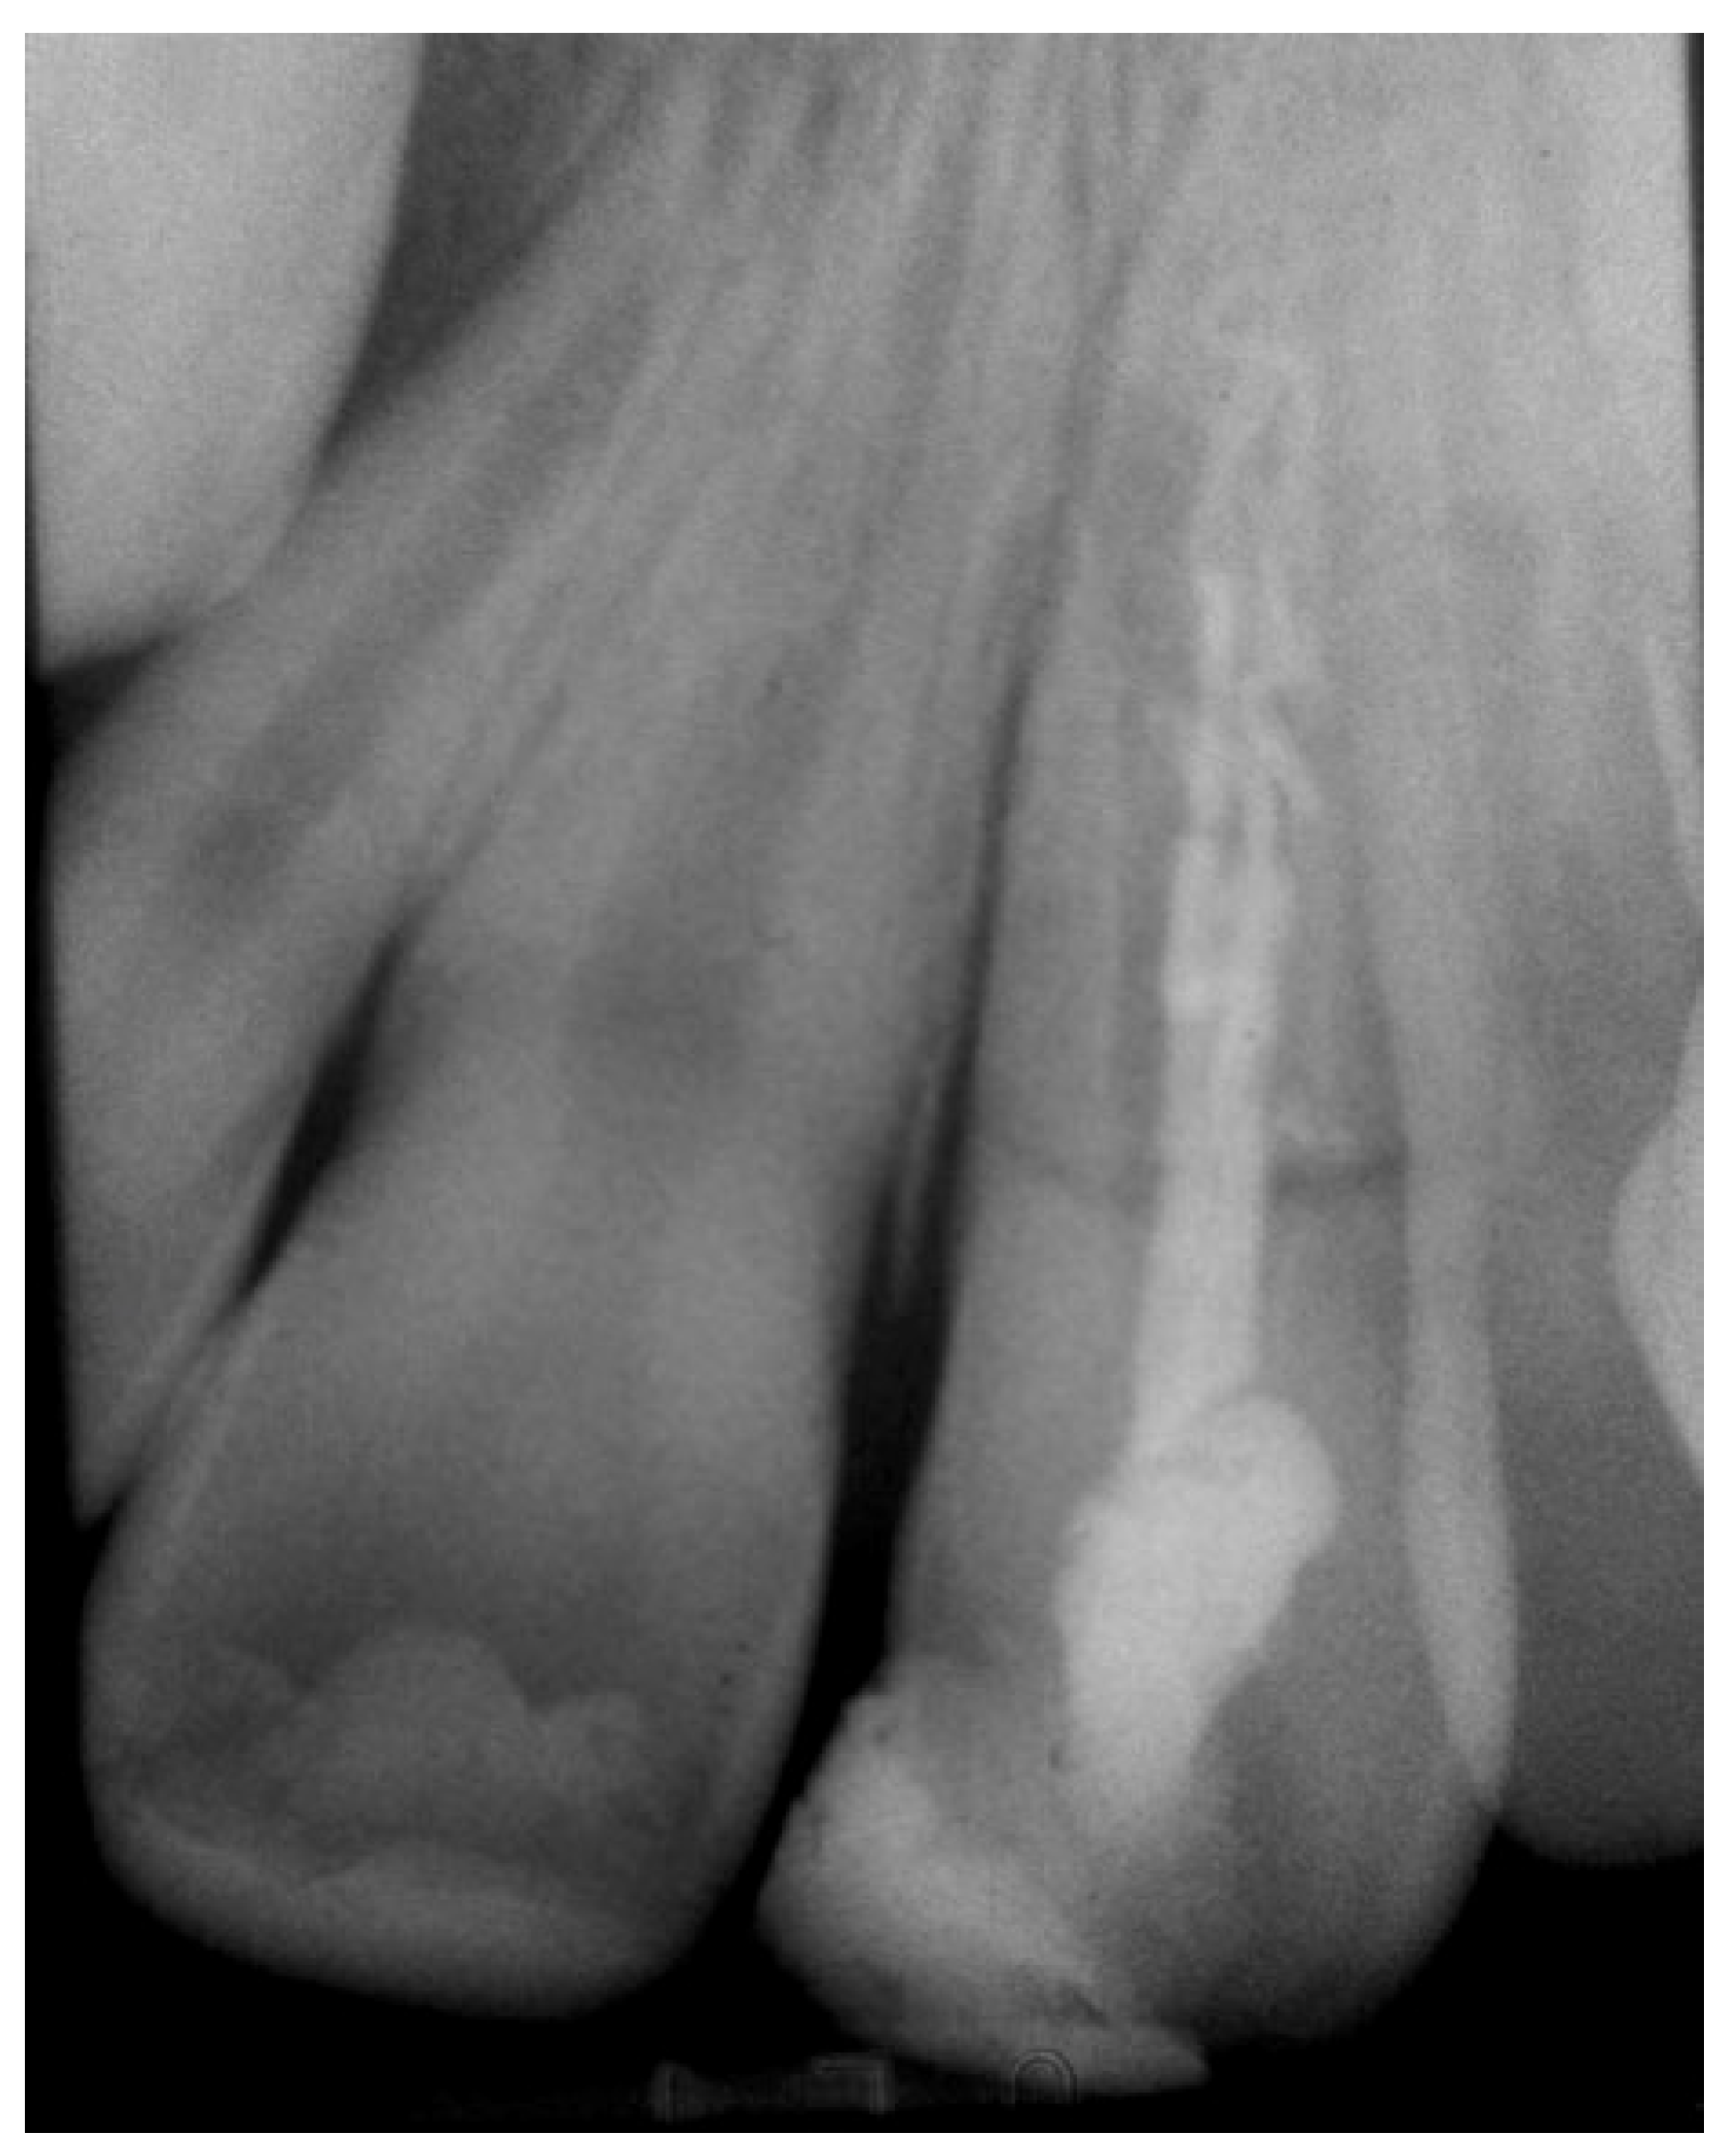

2. Case Presentation